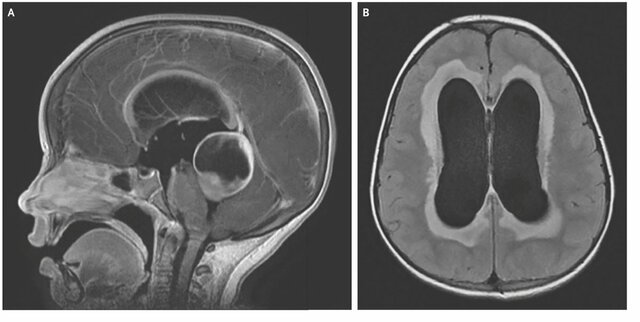

• HIDROCEFALIA

HIDROCEFALIA

Edouard Busch, y el noruego Arn Torkildsen con sus aportaciones técnicas al tratamiento de la hidrocefalia no comunicante.

• Válvulas para tratar la hidrocefalia. Derivaciones

Válvulas para tratar la hidrocefalia. Derivaciones

El colombiano Salomón Hakim, descubre la hidrocefalia normotensiva y desarrolla la válvula unidireccional para tratarla, la cual puede regular la presión, a diferencia de las válvulas ya creadas de Holter y Spitz en eso de los años 50